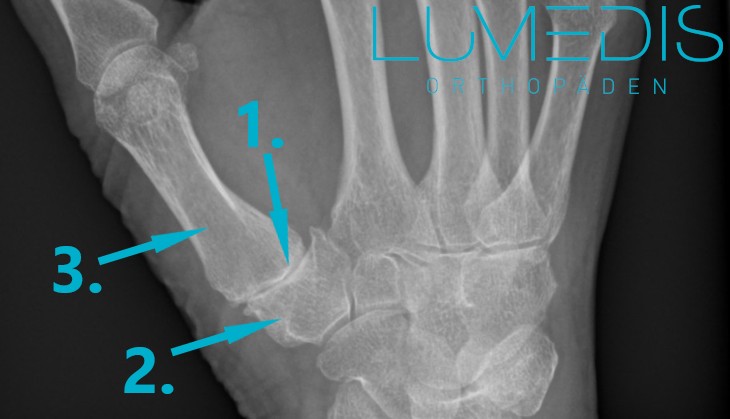

Röntgen einer Rhizarthrose (Arthrose im Daumen) der rechten Hand

Im Röntgenbild lassen sich generell dichte Strukturen wie Knochen oder Verkalkungen besonders gut darstellen. Nicht dichte Strukturen, wie Luft oder zellfreie Bereiche können durch Aussparungen auch gesehen werden (dunkle Areale). Bei der Diagnostik einer Daumensattelgelenksarthrose macht man sich beides zu nutze.

Der Daumen wird im Ganzen und gelenksnahe geröntgt.

Bei einer Daumensattelgelenksarthrose sieht man folgende Vernderungen im Röntgenbild: